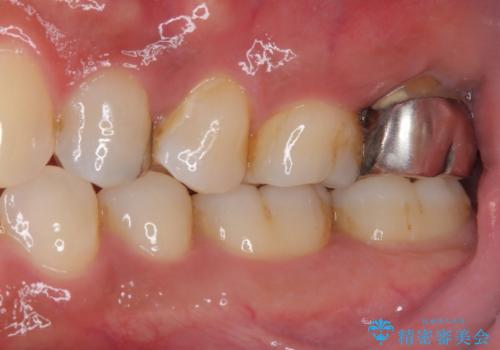

- 奥歯の周りの歯肉が腫れており、噛む度に痛みを感じるとのことで来院された患者様です。

ご自身の感覚として、抜歯は免れないと判断されており、インプラント治療を希望されていました。

レントゲンや診察を行ったところ、抜歯となる可能性はありましたが、まずは銀歯を外した上で根管治療を行うことが可能であるか判断することが先決であるとご説明し、根管治療とインプラント治療の双方をご案内し、治療を開始することとしました。

骨の透過像が非常に大きく、根管も大きく削られていたため、歯根破折による抜歯の可能性がありましたが、根管治療可能な状態でした。

初回治療後には速やかに痛みが改善され、非常に大きかったレントゲンでの骨透過像も改善されました。